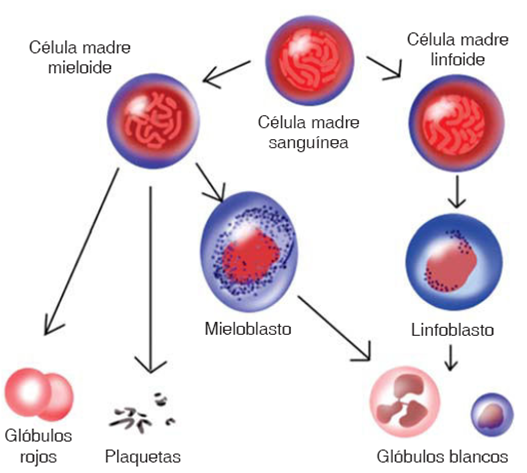

Sin embargo, además de la citogenética existen otros factores que condicionan el pronóstico de la leucemia (Cuadro III).